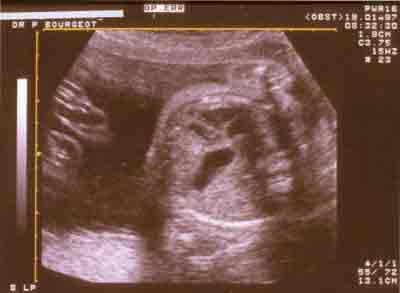

Hernie diaphragmatique gauche : cœur refoulé, cavités gauches petites, estomac anéchogène